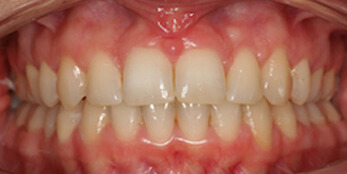

See the smiles we have transformed